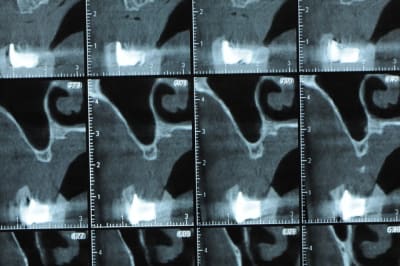

avant de faire la tomosynthèse je comprenais pas pourquoi j'avais aussi peu de contraste.

le patient ne souhaite pas, ou ne peut pas se faire poser 6 implants en haut, donc...overdenture sur 4. (si possible)

Ce n'est pas vraiment un consensus mais plutot du bon sens. Si tu as une crête en profil de lame de couteau cela signifie que tu as une fusion des corticales vestibulaire et palatine et donc absence de spongieux, ce qui comme tu le sais n'est pas indiqué en implanto (cj os de marbre par exemple)

Il me semble que Palti ou encore Szmukler-Moncler recommandent un minimum de 2-3mm. Si c'est plus fin, greffe d'apposition et GBR.

Dans ton cas il te faudrait abaisser la crête de 3 bons mm pour arriver à cette épaisseur.

Une petite étude de ton cas D57

Sous réserves bien sur de voir l’animal en vrai

Les zones exploitables radiologiquement parlant:

Coupes implant

2,3 40100

4,96 35130 avec sinus lift mais difficile

5,25 35150

6,02 35130

6,78 35115 après réduction de hauteur de crête

7,26 35115 après réduction de hauteur de crête

8,51 35150

10,43 40115 ou 50115

11,10 40115

Ce qui nous fait 9 implants possible évidement avec un comblement de sinus on augmenterait encore les zones implantable mais ce n’est pas le but recherché, avec 8 (4+4) il doit être possible de faire une belle barre support de complet